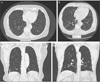

Methods: We performed a blinded assessment of interstitial lung abnormalities detected in 2633 participants in the Framingham Heart Study by means of volumetric chest computed tomography (CT). We evaluated the relationship between the abnormalities and the genotype at the rs35705950 locus.

Results: Of the 2633 chest CT scans that were evaluated, interstitial lung abnormalities were present in 177 (7%). Participants with such abnormalities were more likely to have shortness of breath and chronic cough and reduced measures of total lung and diffusion capacity, as compared with participants without such abnormalities. After adjustment for covariates, for each copy of the minor rs35705950 allele, the odds of interstitial lung abnormalities were 2.8 times greater (95% confidence interval [CI], 2.0 to 3.9; P<0.001), and the odds of definite CT evidence of pulmonary fibrosis were 6.3 times greater (95% CI, 3.1 to 12.7; P<0.001). Although the evidence of an association between the MUC5B genotype and interstitial lung abnormalities was greater among participants who were older than 50 years of age, a history of cigarette smoking did not appear to influence the association.